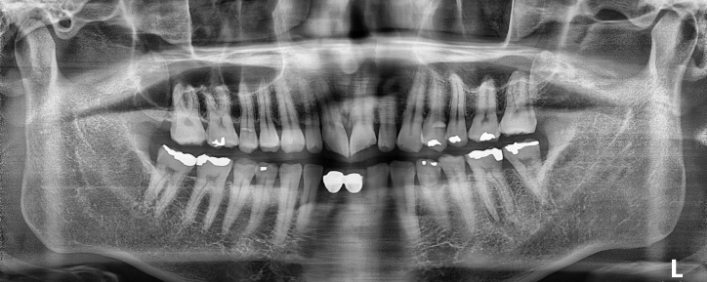

박** 환자분 (오른쪽 상하악 사랑니 동시 발치 케이스)

상악의 경우 단순매복으로 발치 및 동시에 하악 잇몸뼈에

깊게 박혀잇는 고난이도 케이스, 잇몸절개 후 치아 분리하여

발치하였으며